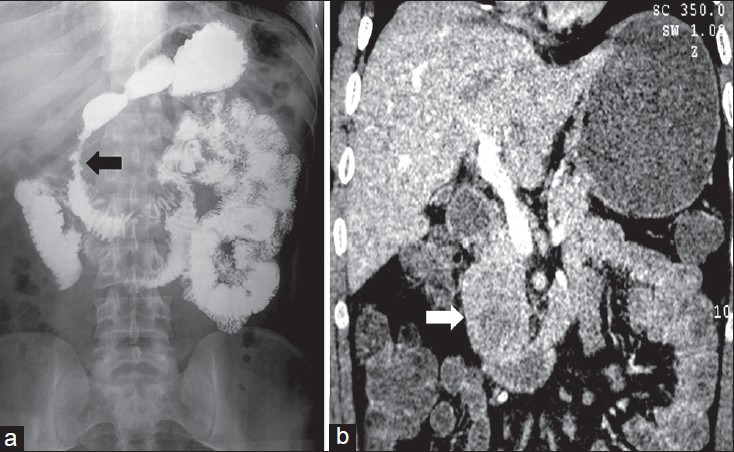

| Figure 11:Cystic gastrointestinal stromal tumors in a 51-yearold male — (a) barium meal follow through spot image showing displacement of terminal ileal loops (arrow) with extrinsic impression and obtuse angles (b) coronal contrast-enhanced computed tomography image showing cystic mass (arrow) arising from the ileal loop (arrowhead)

| Figure 11:Cystic gastrointestinal stromal tumors in a 51-yearold male — (a) barium meal follow through spot image showing displacement of terminal ileal loops (arrow) with extrinsic impression and obtuse angles (b) coronal contrast-enhanced computed tomography image showing cystic mass (arrow) arising from the ileal loop (arrowhead)